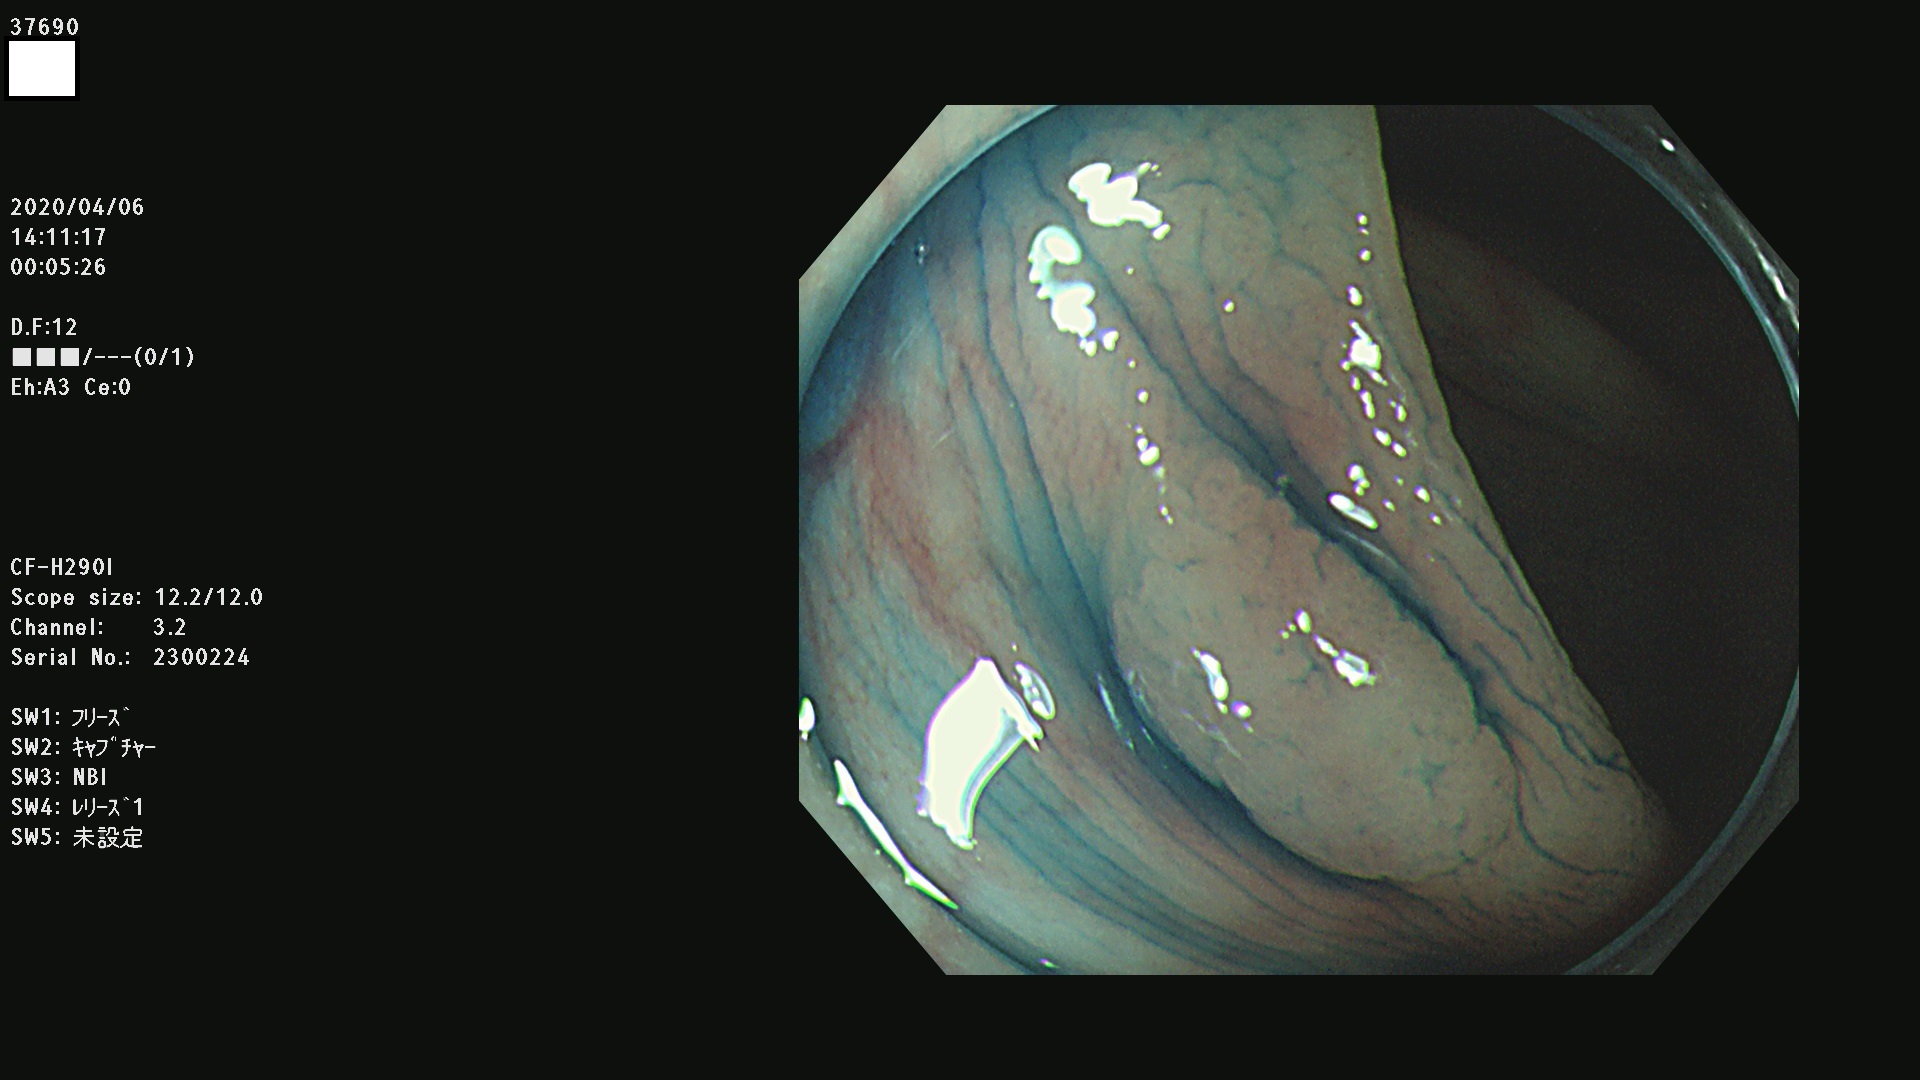

37600 37601 37602 37603 37604 37605 37606 37607 37608 37612 37614 37616 37618 37619 37620 37621 37622(SSAPのみ) 37623(SSAPのみ) 37624 37626 37627 37628 37629 37632 37633 37635 37636(SSAPのみ) 37639 37640 37641 37642 37643 37644 37647(SSAPのみ) 37648 37649 37650 37652 37653 37655 37657 37659 37660 37662 37664 37666 37668(SSAPのみ) 37670 37671 37672 37676 37677 37678 37679 37680 37682 37684 37685(SSAPのみ) 37686 37687 37688 37689 37690 37691 37692(SSAPのみ) 37693 37694 37695 37696 37697 37699

発見困難で危険性の高い平坦型病変(上記100名より抽出)